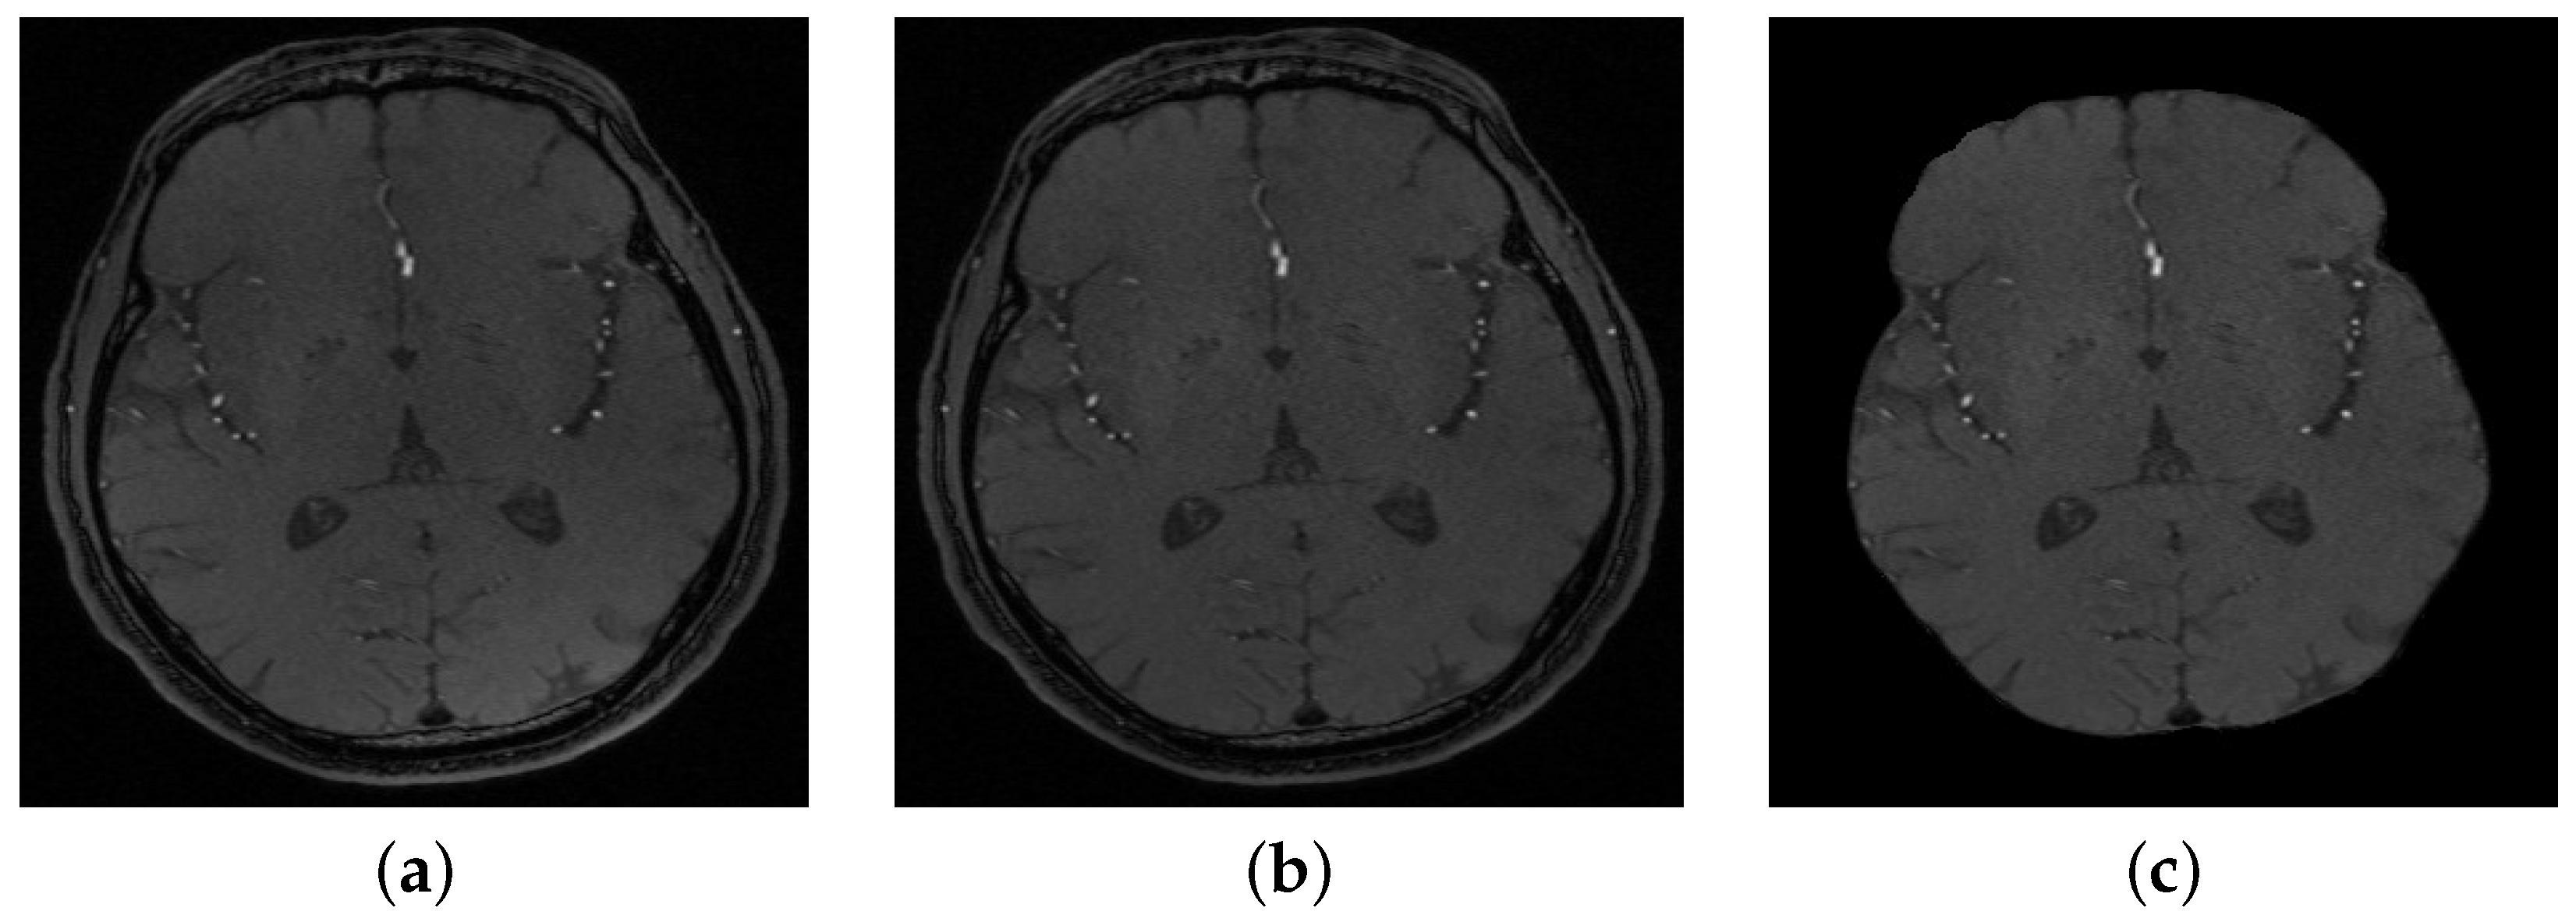

Figure 2. (a) A sample of a 2D original slice, (b) after bias correction, and (c) after skull stripping.

The segmentation of cerebral vasculature started with a linear combination of discrete Gaussians to estimate the marginal probability density of MRA voxel values for vessels and other brain tissues [18,19]. This results in an initial delineated vasculature that misses some details of the cerebrovasculature such as tiny blood vessels. To enhance the initial segmented vasculature, a 3D adaptive segmentation method was used [20]. This algorithm works by dividing each MRA slice into a set of connected components. A search window of adaptive size was centered around each component in the set and a new separation threshold was calculated as T = μ b + μ o 2 , where μ b is the intensity average of cerebral vessels and μ o is the intensity average of other cerebral tissues. Additionally, a seed-generation refinement procedure was applied to detect potential seeds within regions with a high potential to contain small cerebral vessels that might have been missed in the initial delineated vasculature. Finally, a 3D region growing connected components algorithm was used to obtain the final vasculature. This algorithm achieved 92.23 % Dice similarity coefficient, 94.82 % sensitivity, and 99.0 % specificity. A preprocessing sample is shown in Figure 2, and a segmentation sample output is shown in Figure 3.